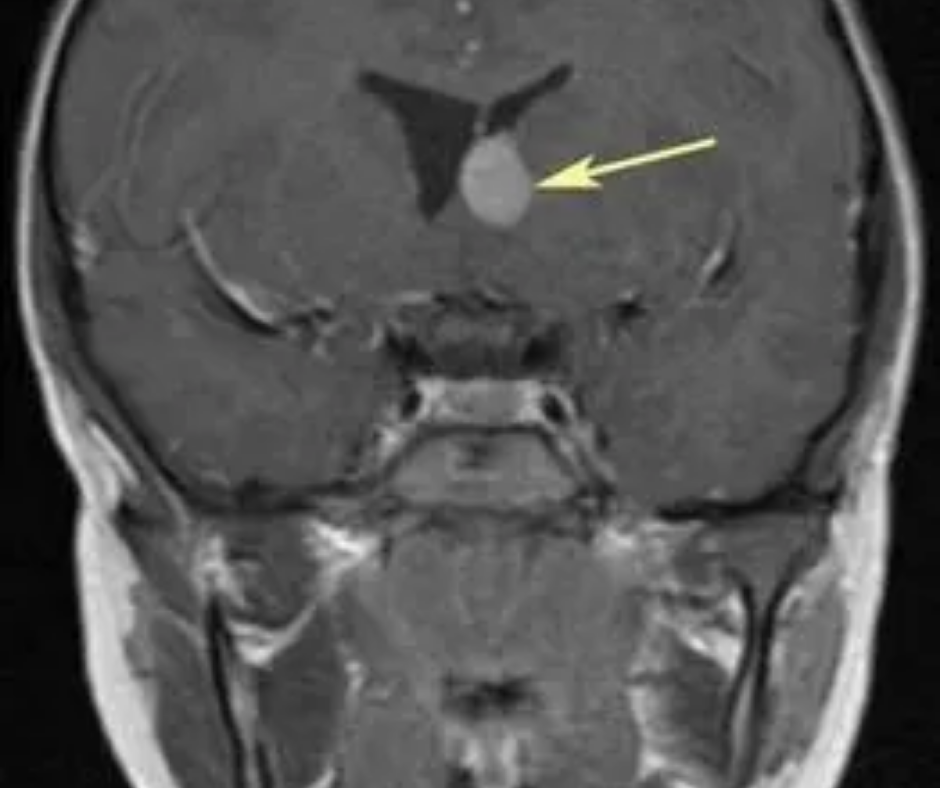

Астроцитома рецидив

Астроцитома рецидив 115 фотографий